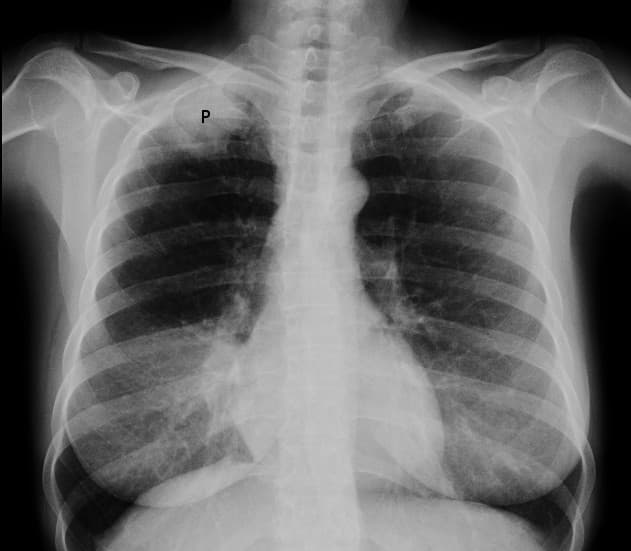

A Pancoast tumor is a tumor of the apex of the lung. It is a type of lung cancer defined primarily by its location situated at the top end of either the right or left lung. It typically spreads to nearby tissues such as the ribs and vertebrae. Most Pancoast tumors are non-small-cell lung cancers. The growing tumor can cause compression of a brachiocephalic vein, subclavian artery, phrenic nerve, recurrent laryngeal nerve, vagus nerve, or, characteristically, compression of a sympathetic ganglion (the stellate ganglion), resulting in a range of symptoms known as Horner's syndrome. Pancoast tumors are named for Henry Pancoast, an American radiologist, who described them in 1924 and 1932. Aside from constitutional symptoms of cancer such as malaise, fever, weight loss and fatigue, Pancoast tumor can include a complete Horner's syndrome in severe cases: miosis (constriction of the pupils), anhidrosis (lack of sweating), ptosis (drooping of the eyelid), and pseudoenophthalmos (as a result of the ptosis). In progressive cases, the brachial plexus is also affected, causing pain and weakness in the muscles of the arm and hand with a symptomatology typical of thoracic outlet syndrome. The tumor can also compress the recurrent laryngeal nerve and from this a hoarse voice and "bovine" (non-explosive) cough may occur. In superior vena cava syndrome, obstruction of the superior vena cava by a tumor (mass effect) causes facial swelling cyanosis and dilatation of the veins of the head and neck. A Pancoast tumor is an apical tumor that is typically found in conjunction with a history of smoking tobacco. The clinical signs and symptoms may be mistaken for neurovascular compromise at the level of the superior thoracic aperture. The patient's smoking history, rapid onset of clinical signs and symptoms, and pleuritic pain can suggest an apical tumor. A Pancoast tumor can give rise to both Pancoast syndrome and Horner's syndrome.